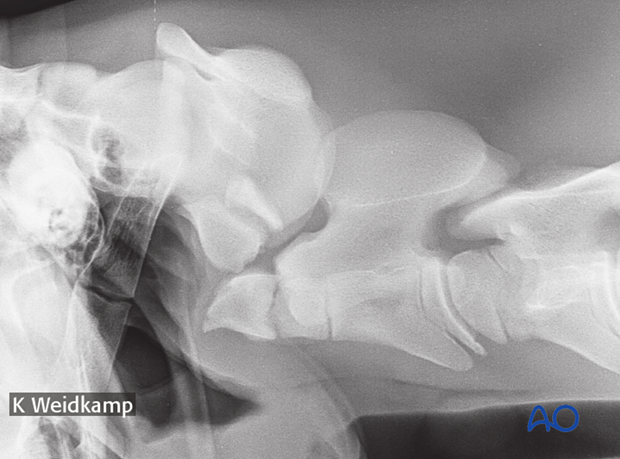

7-year-old Hanoverian Horse with a cranial C2 fracture not involving the dense, caused during a fall in a show jumping competition.

For the treatment of this fracture the same technique as described for a dens fracture would be applied.